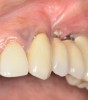

Whether or not to probe around dental implants has been a topic of debate in the dental community for years. Recent consensus supports periodic probing around dental implants so that changes in probing, such as the presence of bleeding on probing, suppuration, and probing depth, can be identified over time.5 If bleeding on probing is present, then the cause(s) of this bleeding should be identified and a proactive treatment approach taken before bone loss begins to occur around the implant. Bleeding may result from poor oral hygiene or a lack of adequate keratinized tissue around the implant (Figure 2). And insufficient keratinized tissue in the presence of poor oral hygiene may lead to an even greater level of peri-implantitis.6 This can result in increases in gingival bleeding, plaque index, pocket depth, and bleeding on probing. Therefore, the presence of adequate thickness and keratinization of soft tissue around dental implants is a necessity.